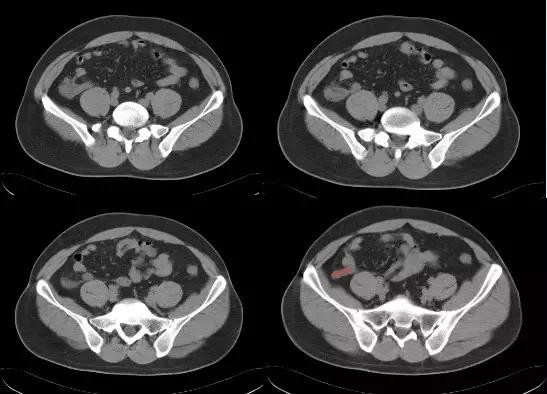

1. 回肠前位:尖端指向左上方

2. 盆位:尖端指向盆腔

3. 盲肠下位:尖端指向右下方

4. 回肠后位:在回肠后位,指向脐

5. 外侧位:位于腹腔内,盲肠外侧